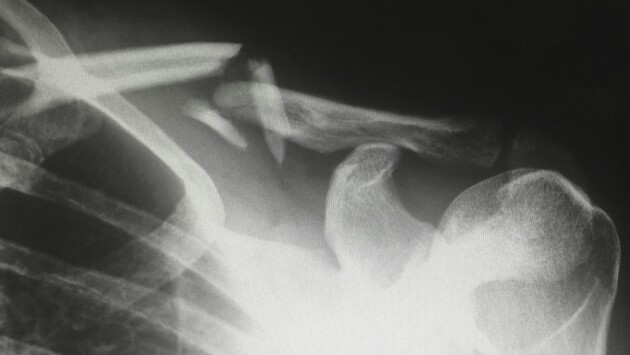

• Частые переломы при незначительных воздействиях и повторные переломы;

• Переломы в анамнезе;